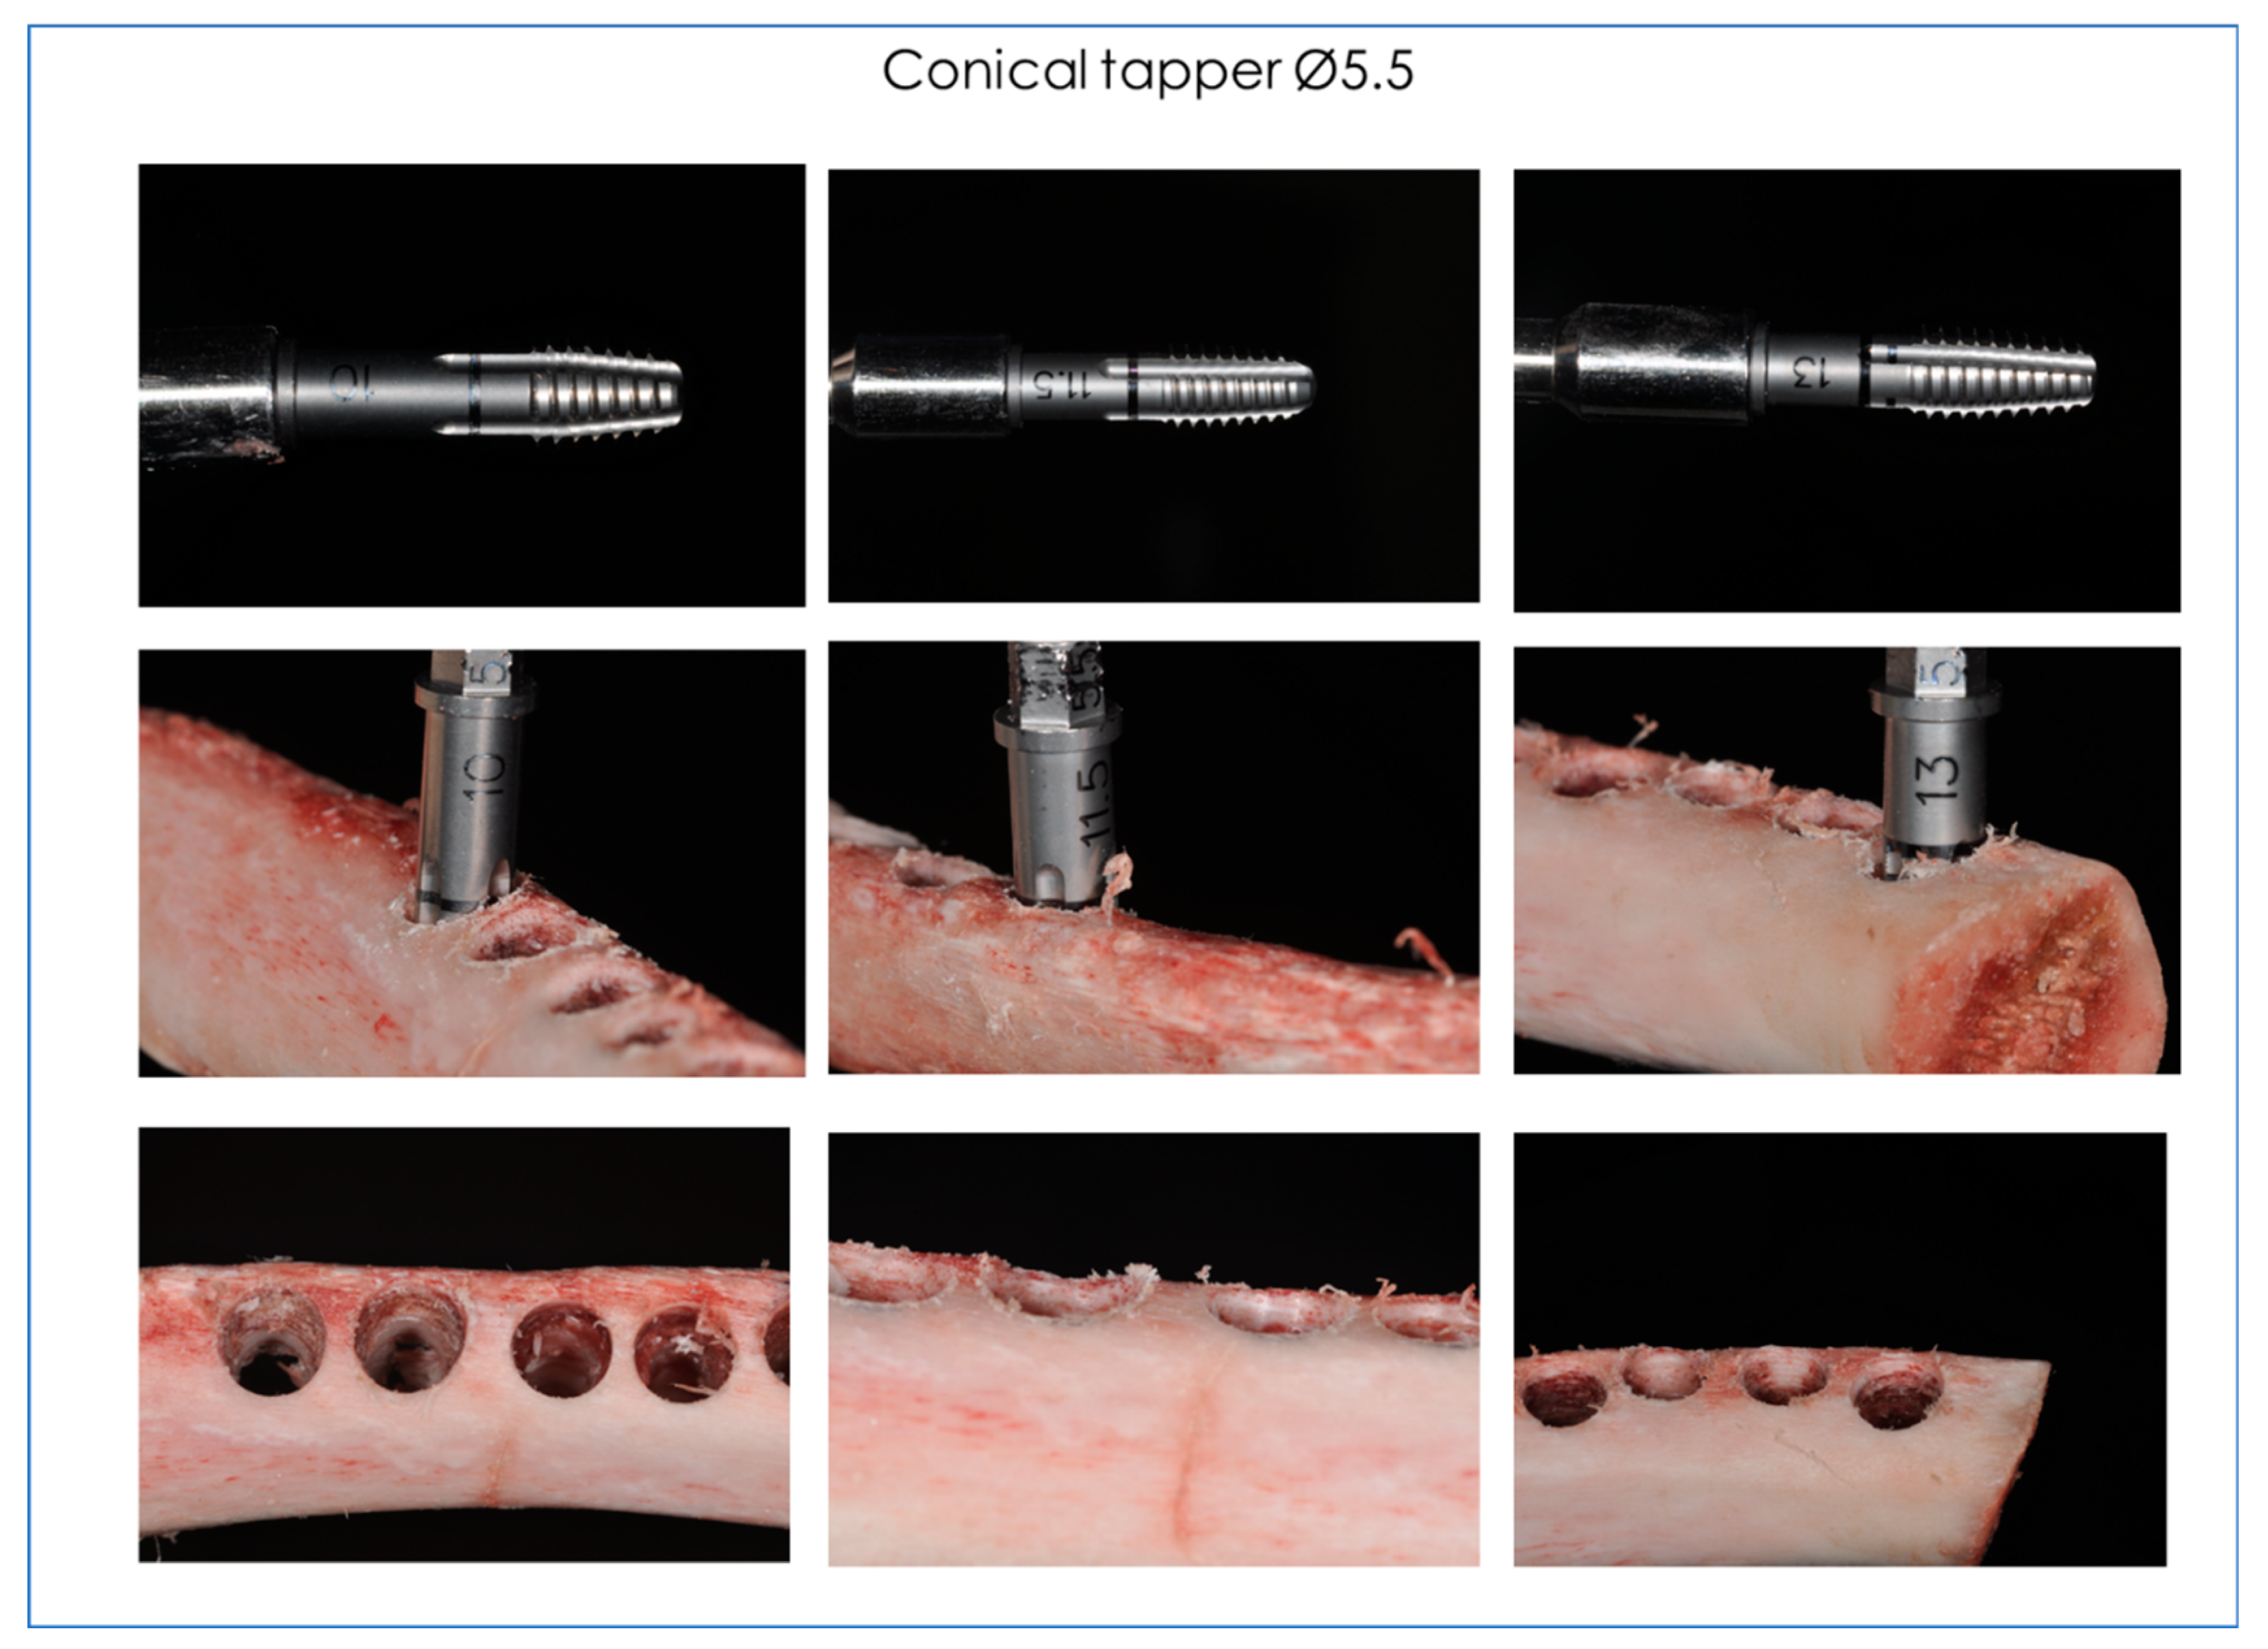

2. Materials and Methods

2.1. Drills and Bone Tappers Evaluated

- MKN3710 Conical tapper Ø3.75 L 10 (Dental Tech, Misinto MB, Italy).

- MKN3711 Conical tapper Ø3.75 L 11.5 (Dental Tech, Misinto MB, Italy).

- MKN3713 Conical tapper Ø3.75 L 13 (Dental Tech, Misinto MB, Italy).

- MSL5510 Conical tapper Ø5.5 L 10 (Dental Tech, Misinto MB, Italy).

- MSL5511 Conical tapper Ø5.5 L 11.5 (Dental Tech, Misinto MB, Italy).

- MSL5513 Conical tapper Ø5.5 L 13 (Dental Tech, Misinto MB, Italy).

2.2. Infrared Thermographic Measurements